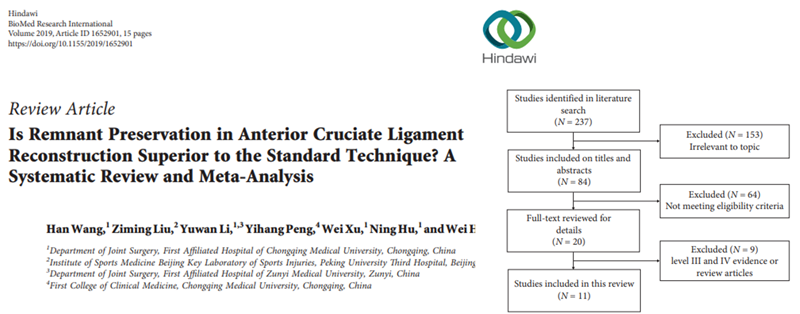

2019年关于前叉保残重建的荟萃分析研究,纳入了2000至2018年12月10日,随访时间超过1年的11篇文章,保残重建能够促进移植物血供和滑膜覆盖,但对膝关节稳定性和术后效果与单纯前叉韧带重建的效果无明显差异。